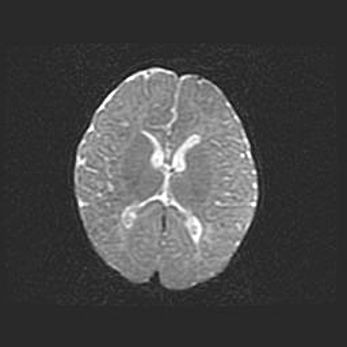

Множественные кисты обоих полушарий головного мозга, наибольшая из них в правой затылочной области. Ассиметричная атрофическая гидроцефалия.

Возраст: 7 месяцев

Вес: 5660 г

Пол: мужской

Окружность головы: 41,5 см

Срок гестации: 28-29 недель

Кисты головного мозга развиваются в результате многоочаговых некрозов вещества мозга и возникают вследствие перенесенной перинатальной инфекции, менингитов, энцефалитов, асфиксии, родовой травмы, расстройств мозгового кровообращения различного генеза. Образованию кист в веществе головного мозга плодов и новорожденных способствуют такие факторы, как высокое содержание в нем воды, недостаточная (или отсутствие) миелинизация и слабая астроглиальная реакция на повреждение.

Кисты могут сочетаться с гидроцефалией и другими поражениями головного мозга.